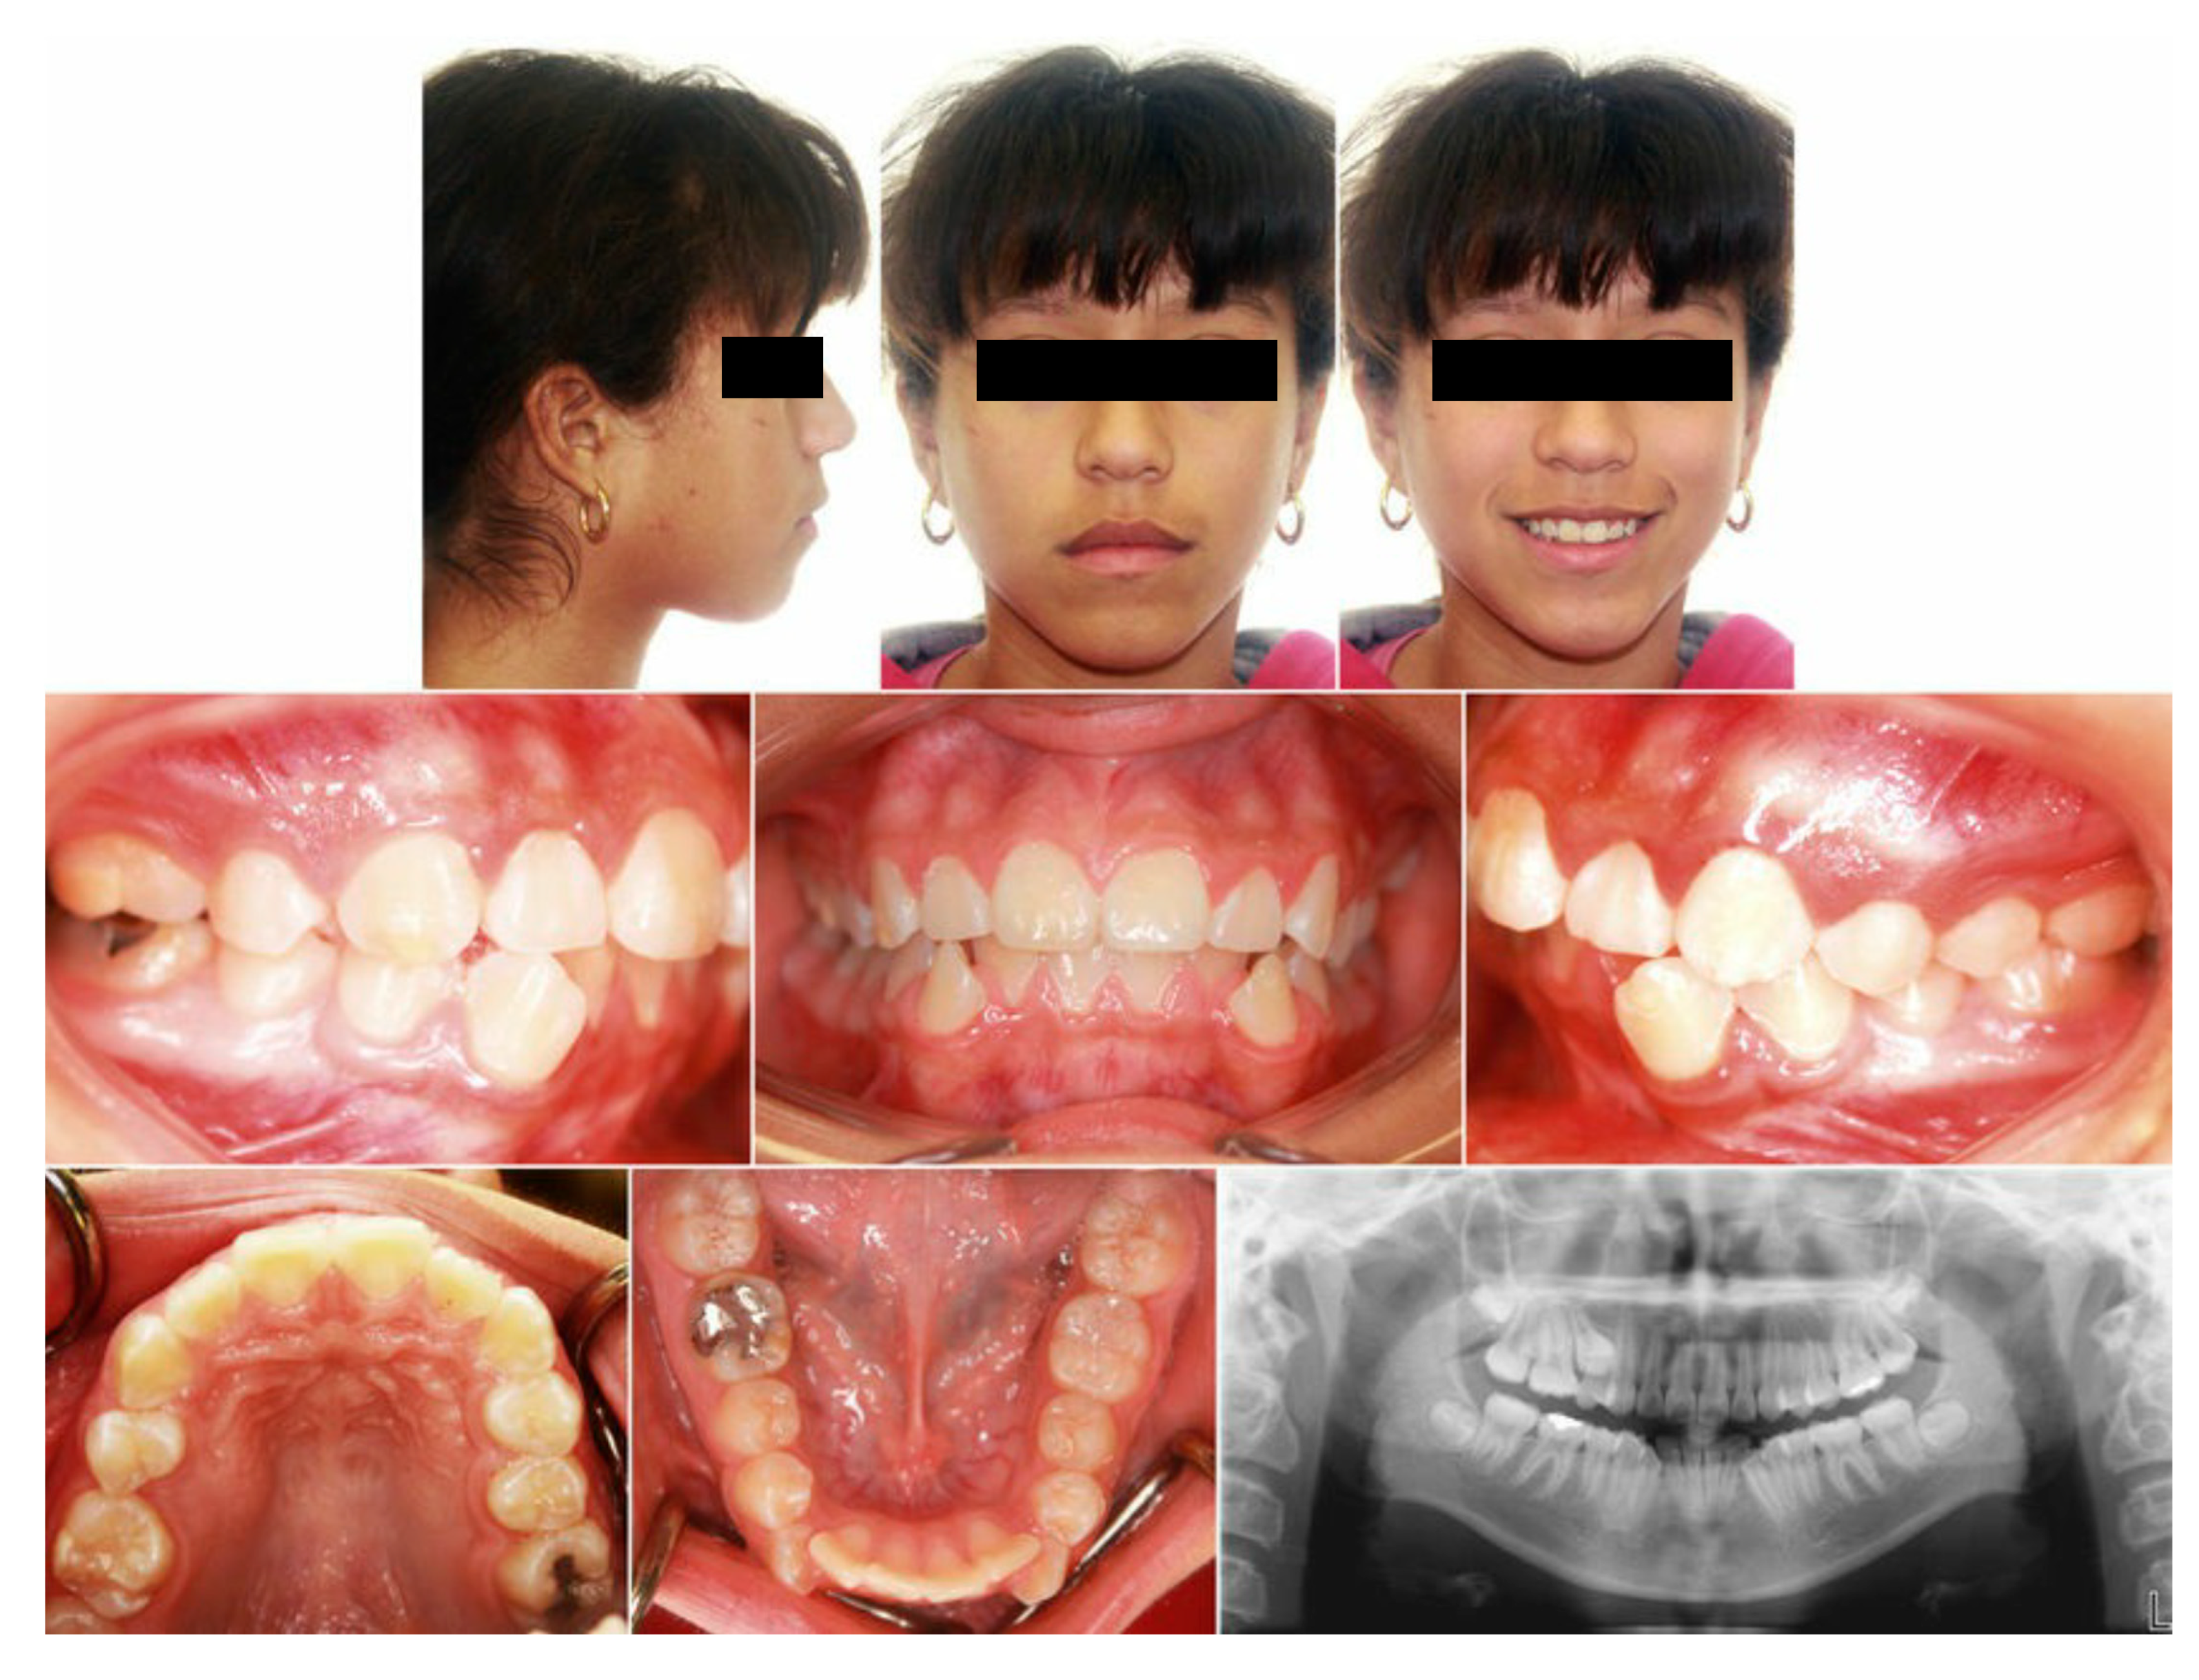

Figure A3.

Full records of the patient.

Table A3.

Demographic data and cephalometric analysis of the case.

| Age | 11 years | Over Jet = 4 mm |

| Sex | Male | Over bite = 8 mm |

| Breathing | Nasal | |

| Cephalometric analysis | ||

| Normal values | Patient values | |

| SNA | 80 | 80.2° |

| SNB | 78 | 75.6° |

| ANB | 2 | +4.3° |

| FMA | 21 | 24.2° |

| SN-GoGn | 32 | 38.1° |

| Maxillary incisor to SN | 105 | 83.3° |

| Mandibular incisor to GoGn | 95 | 83.3° |

| Soft tissue | ||

| Lower lip to E-plane | –2.0 mm | −4.9 mm |

| Upper lip to E-plane | –1.6 mm | −4.4 mm |